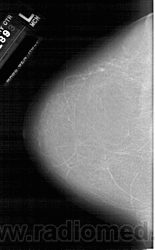

Со старением железистая ткань постепенно исчезает: прозрачность жировой ткани становится преобладающей с несколькими каркасами, связанными с опорными волокнистыми структурами.

Жирная (не плотная) грудь

Умеренно плотная грудь

Плотная грудь

Маммограммы представляют собой изображения структур, проецируемых на плоскость: плотная грудная маммограмма, следовательно, состоит из многих других структур, которые необходимо проанализировать, чем более жирная, пустая грудь. По этой причине диагностировать рак молочной железы труднее для моложе, чем для пожилых женщин.

Нажмите на миниатюрные картинки, чтобы получить увеличенный размер.